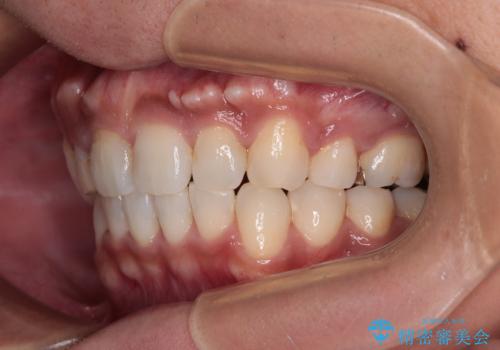

- 上顎の八重歯と正中のズレを気にして来院された患者様です。

八重歯による叢生は著しく、それにより上顎の正中が大きく右にずれている状態でした。

口元の突出感は感じていなかったことと、奥歯の咬み合わせを考慮し、上顎のみ左右の第一小臼歯を抜歯してワイヤー装置にて矯正治療を行うこととしました。